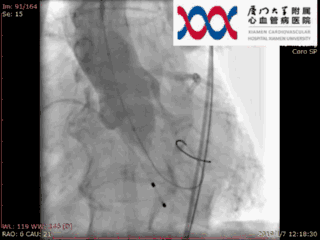

选择23X40mm球囊预扩

瓣膜释放后造影

多年的病史,让庄爷爷深刻体会疾病带来的痛苦。现在庄爷爷活动力明显下降,除了静卧休息,动动就觉得气促难受。由于庄爷爷已是98岁高龄,若进行外科开胸手术会大大增加术后死亡率和并发症的发生风险。对于庄爷爷的病情,厦门大学附属心血管病医院心脏团队联合麻醉科,心超科,放射科,手术室,重症监护室等多学科对术前准备,手术方案及术后护理等进行详细讨论。2019年1月7日,王焱院长及王斌主任心脏团队为庄爷爷实施了经股动脉主动脉瓣置换术,手术非常顺利。瓣膜释放后心超及造影显示跨瓣压差0mmHg,无瓣周漏,无返流。这是目前国内接受经股动脉主动脉瓣置换微创手术的最高龄患者。